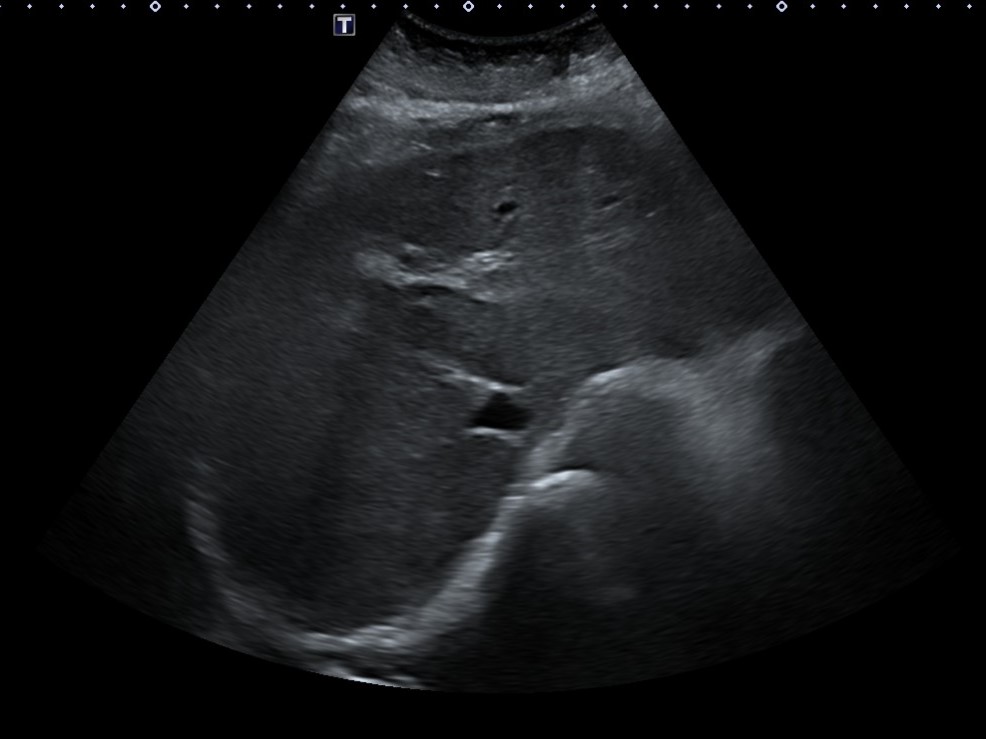

Ante resultados analíticos se realiza ecografía clínica a pie de cama. Se evidencia parénquima hepático de consistencia irregular con lesiones hipoecoicas sugestivas de metástasis tumorales. Se solicita estudio reglado.

En TC abdominal-pélvico informan:

Múltiples lesiones hipodensas hepáticas en probable relación con metástasis sin poder descartar sobreinfección de las mismas dado los datos clínicos aportados. Adenopatías retroperitoneales patológicas.